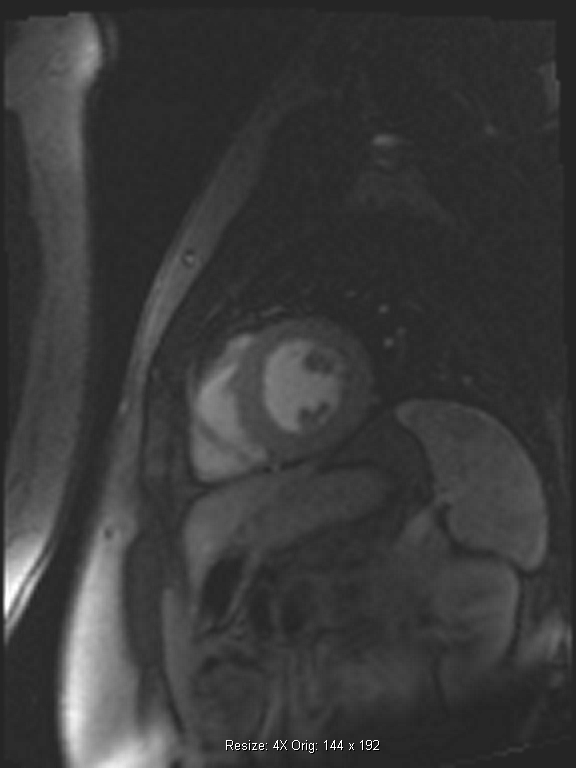

Οι νεότερες τεχνικές που εφαρμόζονται στο Τμήμα Μαγνητικής Τομογραφίας Καρδιάς του Μetropolitan Hospital είναι η δυναμική μαγνητική τομογραφία καρδιάς με αδενοσίνη (adenosine stress perfusion MRI), μια δυναμική τεχνική με υψηλή ειδικότητα, ευαισθησία, διακριτική ικανότητα και ασφάλεια και η μαγνητική τομογραφία καρδιάς με χαρτογράφηση του μυοκαρδίου (Τ1/Τ2 mapping MRI), μια συμπληρωματική απεικονιστική μέθοδος που δίνει περισσότερες πληροφορίες με ασφάλεια σε περιπτώσεις αντένδειξης της χρήσης σκιαγραφικού ενδοφλεβίως.

Δυναμική μαγνητική τομογραφία καρδιάς με αδενοσίνη (adenodine stress perfusion MRI)

Οι κυριότερες ενδείξεις της δυναμικής μαγνητικής τομογραφίας καρδιάς με αδενοσίνη είναι:

• ο αποκλεισμός στεφανιαίας νόσου σε άτομα χαμηλού και μέσου κινδύνου

• ο καθορισμός της αιμοδυναμικής σημασίας σε περιπτώσεις με ενδιάμεσες στενώσεις των στεφανιαίων αγγείων κατά την κλασική στεφανιογραφία ή την αξονική στεφανιογραφία

• η μελέτη μυοκαρδιοπαθειών που προκαλούν στηθαγχικά ενοχλήματα και υπενδοκάρδια ισχαιμία

• η μελέτη αιμάτωσης-βιωσιμότητας μετά από έμφραγμα μυοκαρδίου.

Τα βασικότερα πλεονεκτήματα της δυναμικής μαγνητικής τομογραφίας καρδιάς με αδενοσίνη (adenodine stress perfusion MRI) είναι η υψηλότερη ευαισθησία και ειδικότητα σε σχέση με τις υπόλοιπες διαγνωστικές μεθόδους δυναμικής απεικόνισης (σπινθηρογράφημα μυοκαρδίου, stress echo), η καταγραφή ακόμα και μικρών υπενδοκάρδιων ισχαιμικών περιοχών και μυοκαρδιακών ουλών, η καλύτερη διακριτική ικανότητα σε σχέση με το σπινθηρογράφημα του μυοκαρδίου και η ασφάλεια λόγω της απουσίας έκθεσης σε ιονίζουσα ακτινοβολία (εικόνες 1,2).